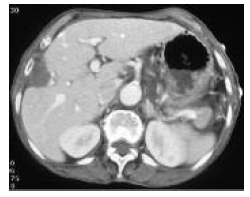

One such combined strategy is the combination of radiofrequency ablation and transarterial chemoembolization. A combination of transarterial chemoembolization followed by radiofrequency ablation has been used to minimize heat loss because of perfusion-mediated tissue cooling and to increase the therapeutic effect of radiofrequency ablation (Figures 5-9).26 Radiofrequency ablation and transarterial chemoembolization are more effective for complete tumor necrosis rate in patients with hepatocellular carcinoma.21,27 Local tumor progression rate was significantly lower in the transarterial chemoembolization and radiofrequency ablation-treated group than in the radiofrequency only ablation group (6%-39%).28

Figure 5 and 6. Hypervascular Hepatocellular Carcinoma Nodule in the Segment V of Liver, and Selective Embolization With Drug Eluting Bead-Transarterial Chemoembolization

Figure 9. One-month Follow-Up, Computed Tomography Images of the Hepatocellular Carcinoma Nodule That Combined (Drug Eluting BeadTransarterial Chemoembolization + Radiofrequency Ablation) Procedure Was Applied. No Residual or Recurrent Lesion